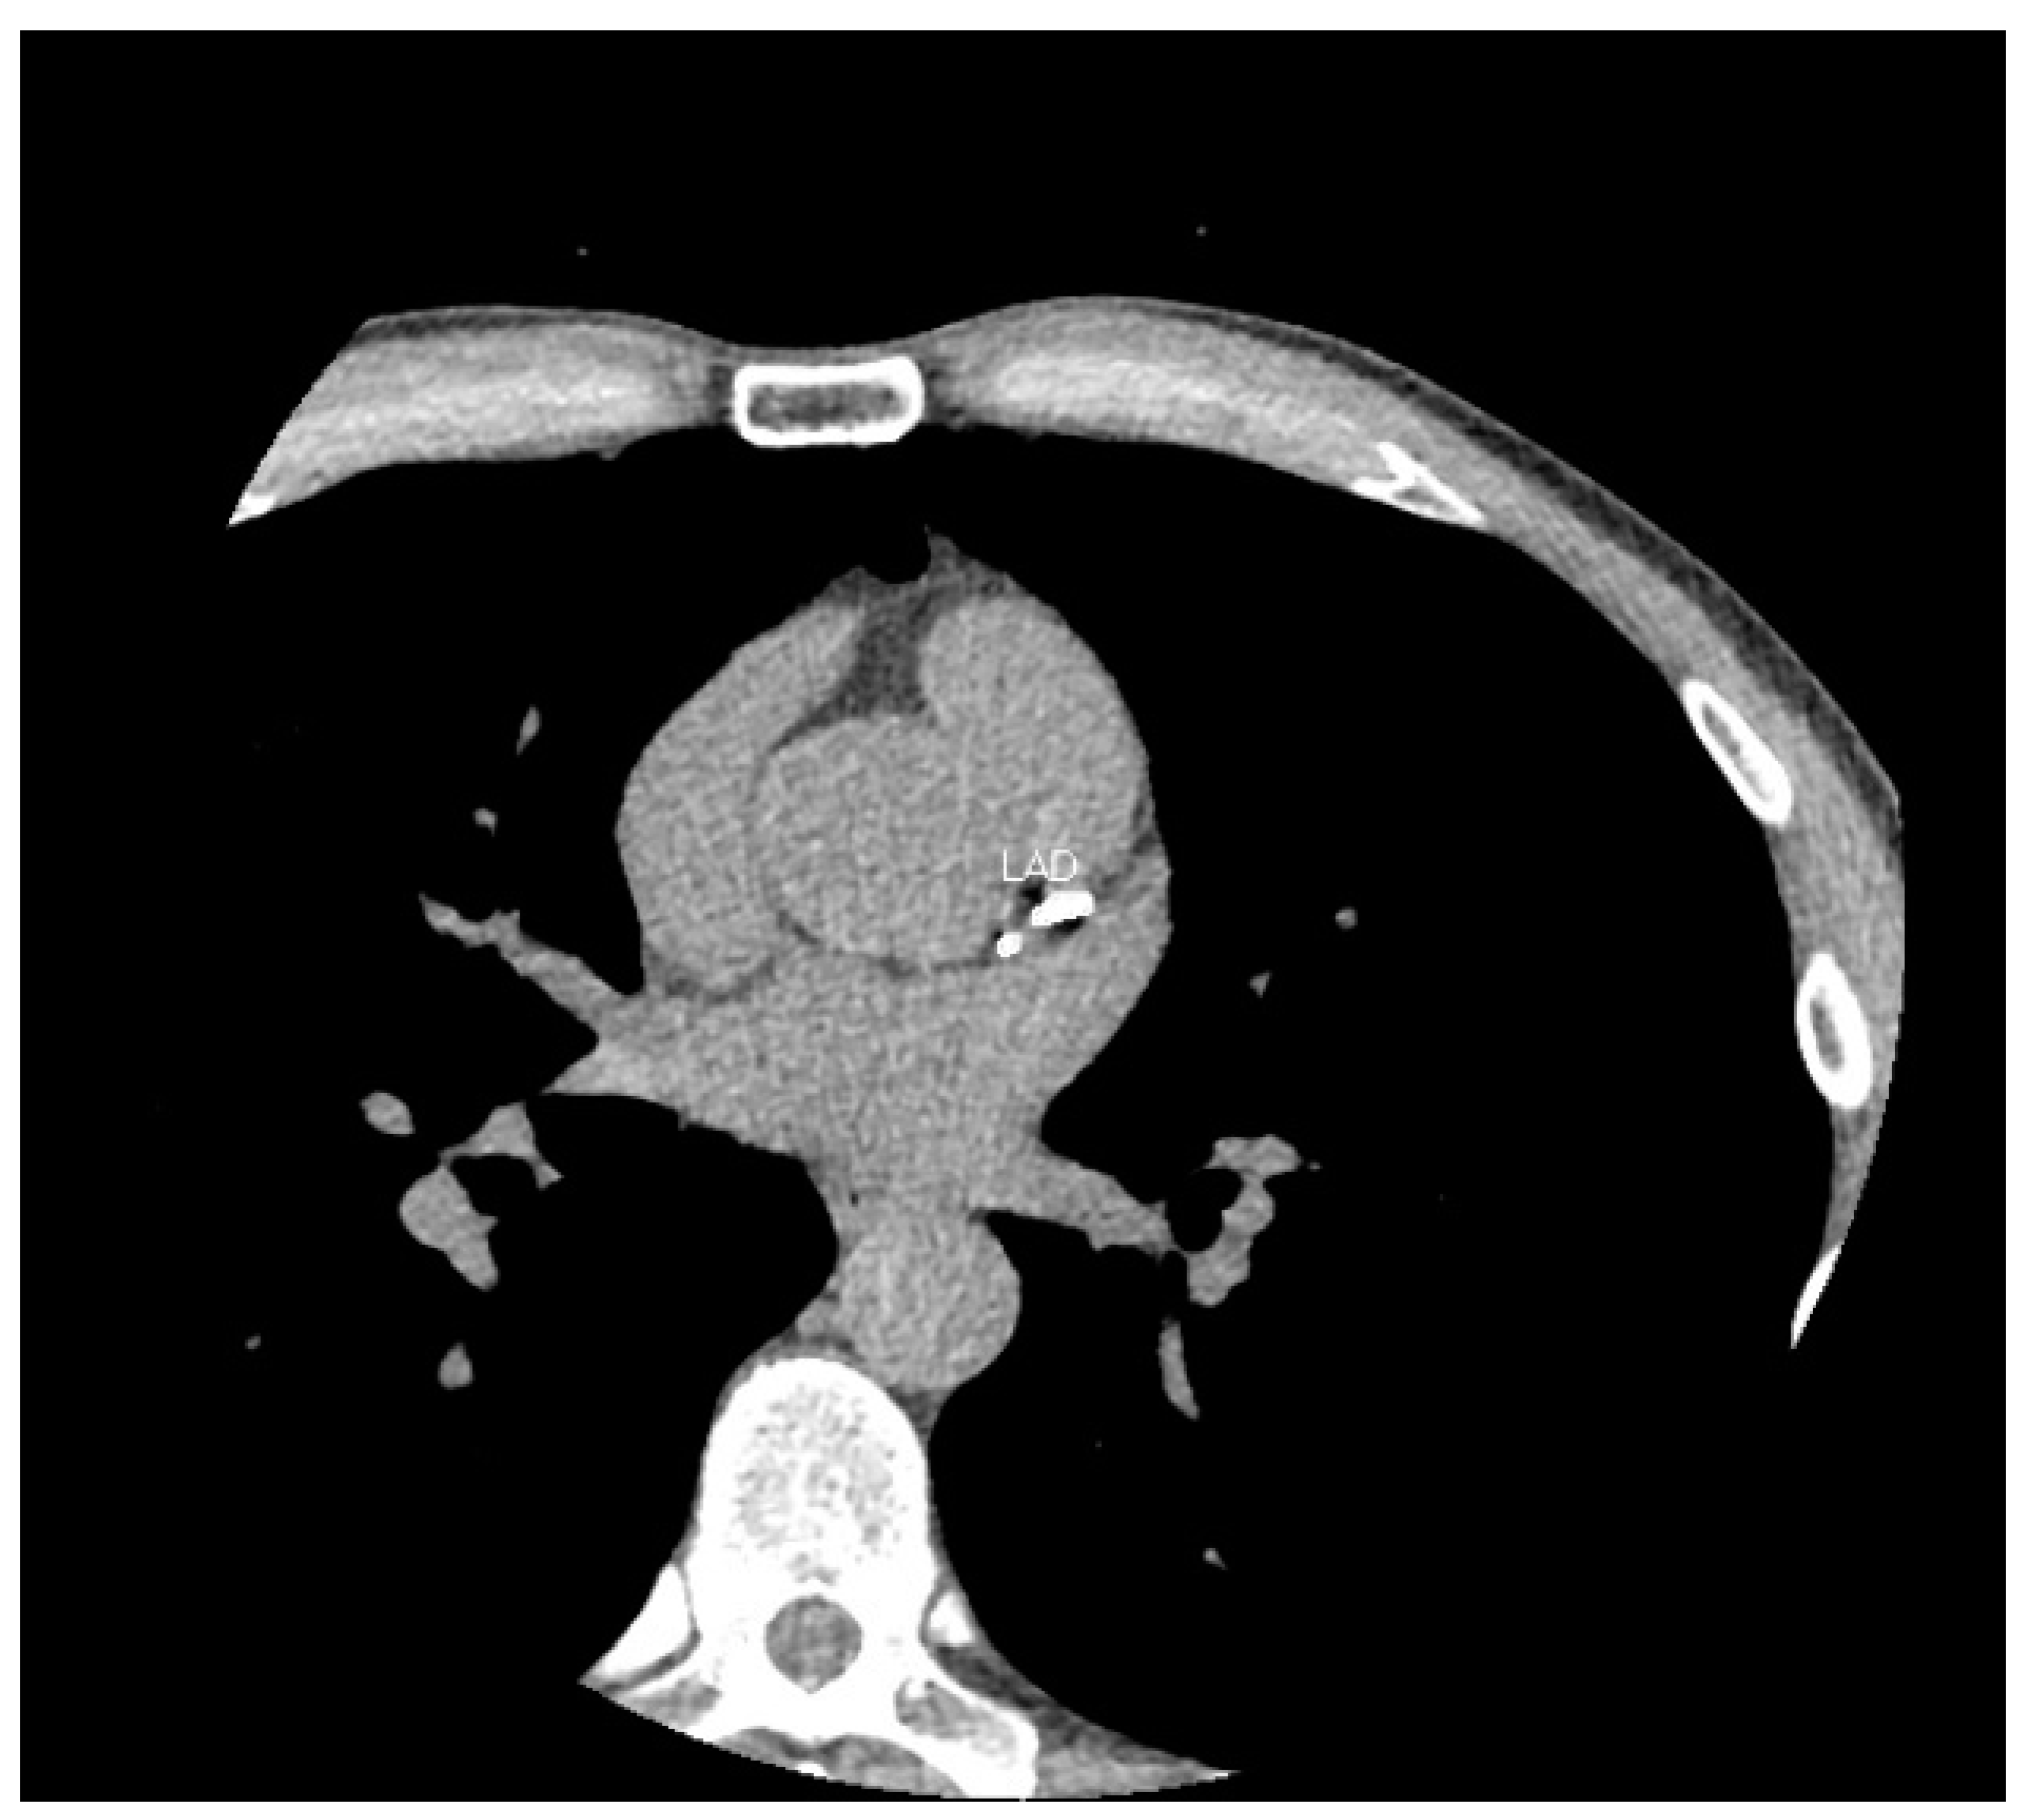

Ischaemic heart disease secondary to coronary artery disease remains one of the leading causes of death worldwide. The burden of atherosclerotic coronary artery disease is directly correlated to the extent of coronary artery calcium (CAC) [1]. CAC can be measured non-invasively using a non-contrast cardiac CT scan (Figure 1) and has been shown to be an independent predicter of cardiovascular events in multiple studies [2,3]. CAC is often performed as a part of CT coronary angiography studies.

Figure 1.

CT calcium score scan. Here is an axial image from a CT calcium score scan of a 51-year-old male. At his age, the majority of males do not exhibit coronary calcification. His total score > 400 places him at greater than the 97th centile for age and gender. The left anterior descending (LAD) artery is labelled.